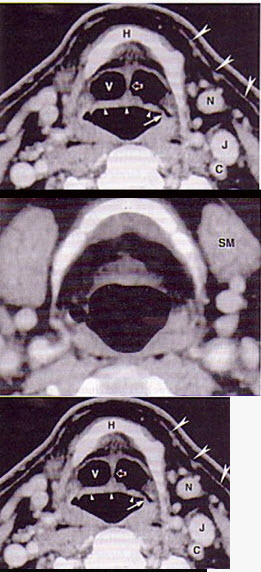

- 单项选择题男,55岁,声嘶6年,有长期吸烟史。检查:无呼吸困难。喉镜检查:声带慢性充血,可见右侧声带可见菜花样新生物,右侧声带活动固定,喉部CT检查如下图: